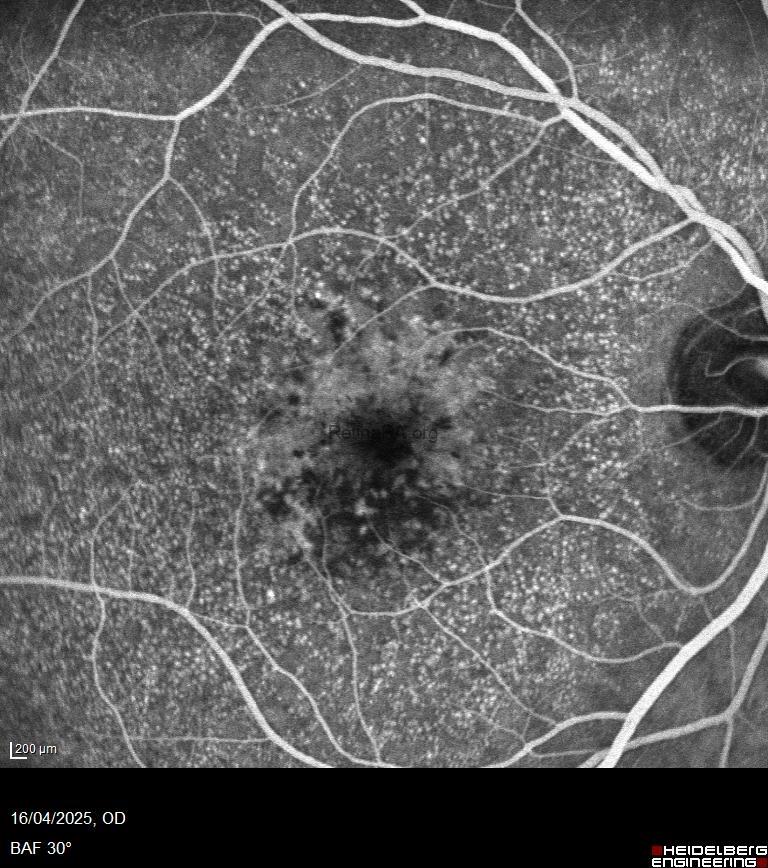

* Fundus Autofluorescence (FAF):

Lesions appear hypoautofluorescent, often bordered by a ring of hyperautofluorescence.